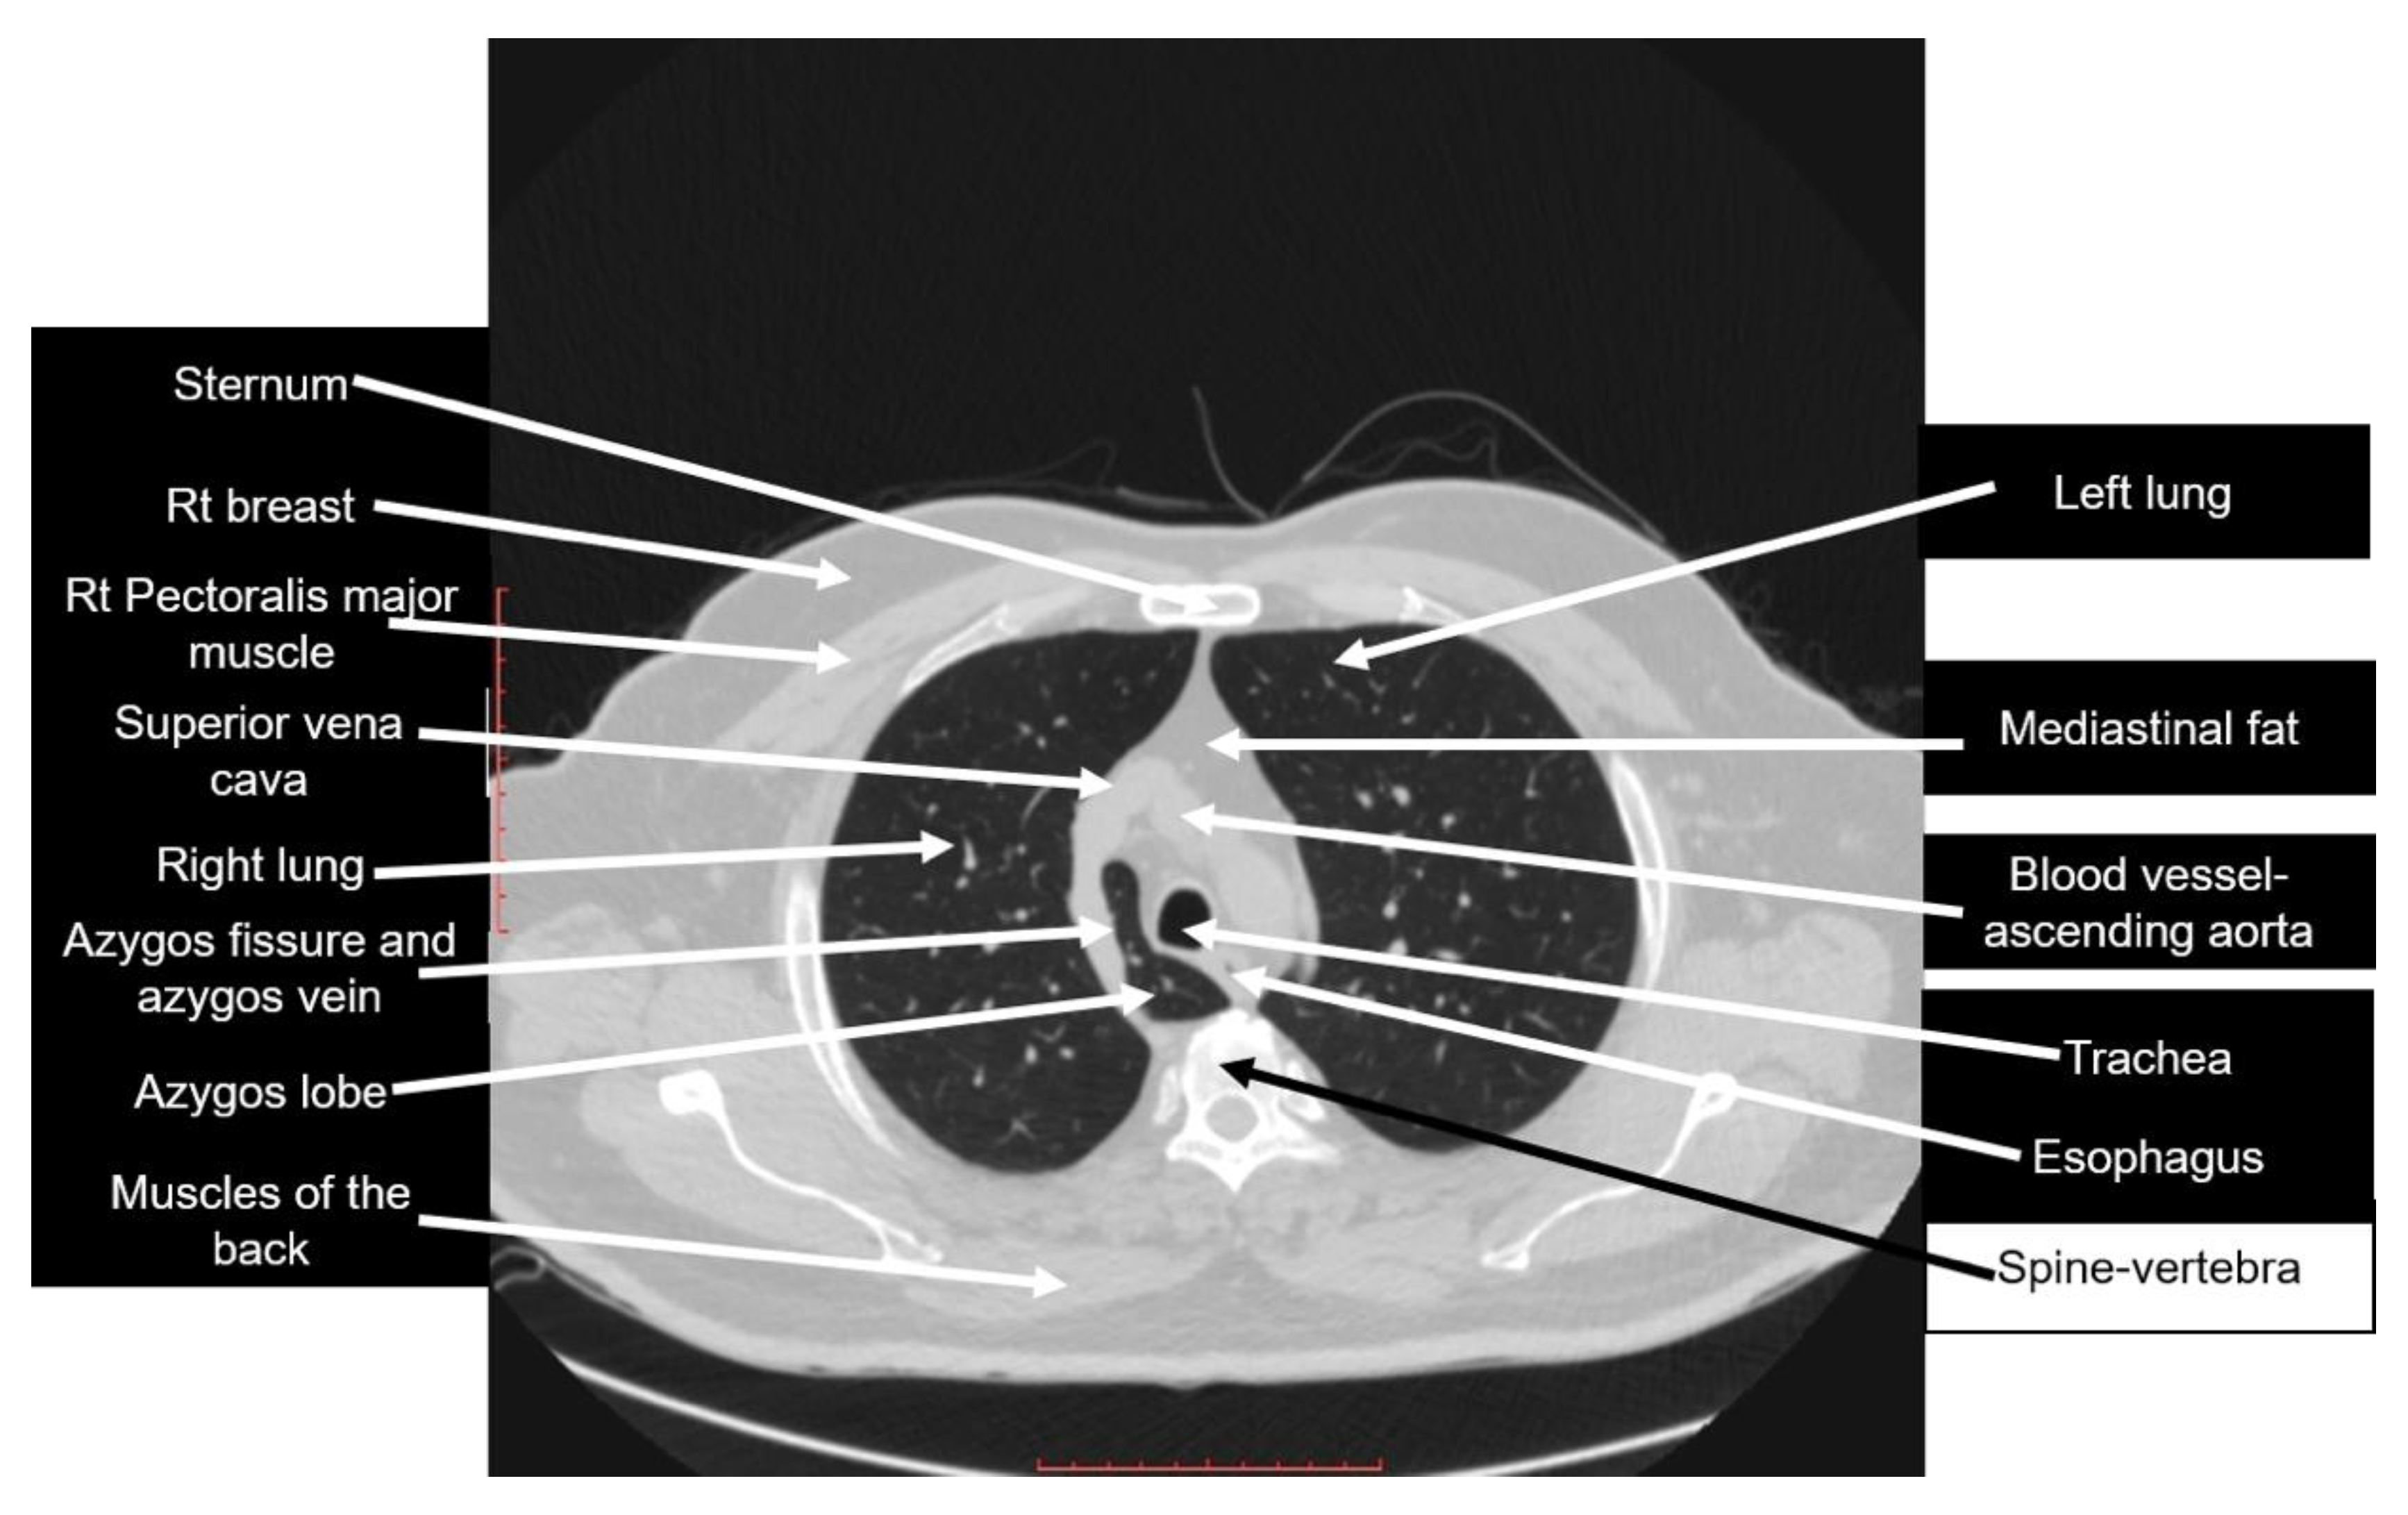

The literature also showed that no previous studies were published on the misconceptions about and misidentifications of the right azygos lobe. As our results showed, the structures that the sample of recruited doctors thought was the azygos lobe, both in the CT scan and in the anatomy image, were ambiguous and bizarre. Figure 3 is the same figure used in the survey, fully labeled.

Figure 3.

Axial CT scan used in the survey, fully labeled. Scale bar = 10 cm.